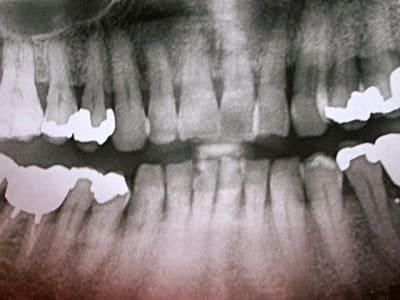

patient, 65 ans, ami proche de la famille, pére d'un très bon ami d'enfance.

douleurs récurrentes au maxillaire droit à la mastication.

sensations de dents + ou - mobiles au max D et mand G.

Je l'ai envoyé faire une pano en attendant de le voir en consultation. Bigre!!!!

Manifestement alvéolyse horizontale généralisée, 25% de perte d'attache à 65 ans : je penche pour une parodontite chronique de l'adulte.

Suffisant s'il n'y avaient pas ces facteurs aggravants que sont les pulpectomies déficientes, couronnes débordantes et mal ajustées.

Je soupçonne aussi un trauma occlusal.

Ouais, l'usure occlusale est quand même flagrante.

moi, c'est la 17 qui me chagrine le plus.

la racine distale de 47 est morte. Première impression: la virer, garder la racine M, petit bridge pro en résine renforcée en attente de stabilisation du pb paro et assurer calage de 48. Voir par la suite pour implant ou bridge.

37: même pas sûr qu'elle soit nécrosée. Si oui, endo assez rapidement (avant soins paro).

36, lésion interradiculaire + distale: hummm...

Déjà on commencera par la base: Bilan général + dentaire + retroalvéolaires au moins sur toutes les postérieures + OHM + modéles d'étude pour analyse occlusale.

Cas typique (enfin je crois) où il est urgent de ne pas extraire, ni de se jeter sur le bistouri si on se met dans un "esprit paro" et que la compliance du patient est ok, sauf 18 (dent courte + carie M) et 17??? mais risque de déporter toutes les forces de mastication à G et c'est la 37 qui va devenir douloureuse.